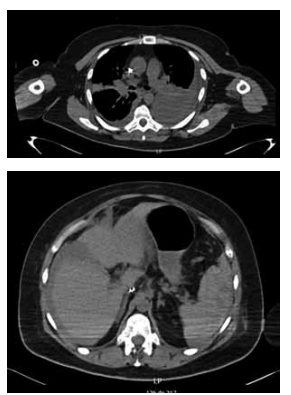

Mulher de 65 anos, com necessidade de toracocentese

de alívio por extenso derrame pleural à esquerda, que

causava dispneia. Realizada punção no 8o

espaço intercostal, linha axilar média, com saída de 20 mL de líquido serossanguinolento, sem saída adicional de líquidos.

Trinta minutos após o procedimento, a paciente evolui

descorada, com frequência cardíaca de 100 bpm e PA

de 85 x 60 mmHg, queixando-se de dispneia e dor abdominal. Realizou a tomografia demonstrada nas imagens

a seguir:

No retorno da tomografia, a paciente evolui com queda do nível de consciência, sendo realizada intubação orotraqueal. Assim, qual conduta mais adequada para resolução do caso?